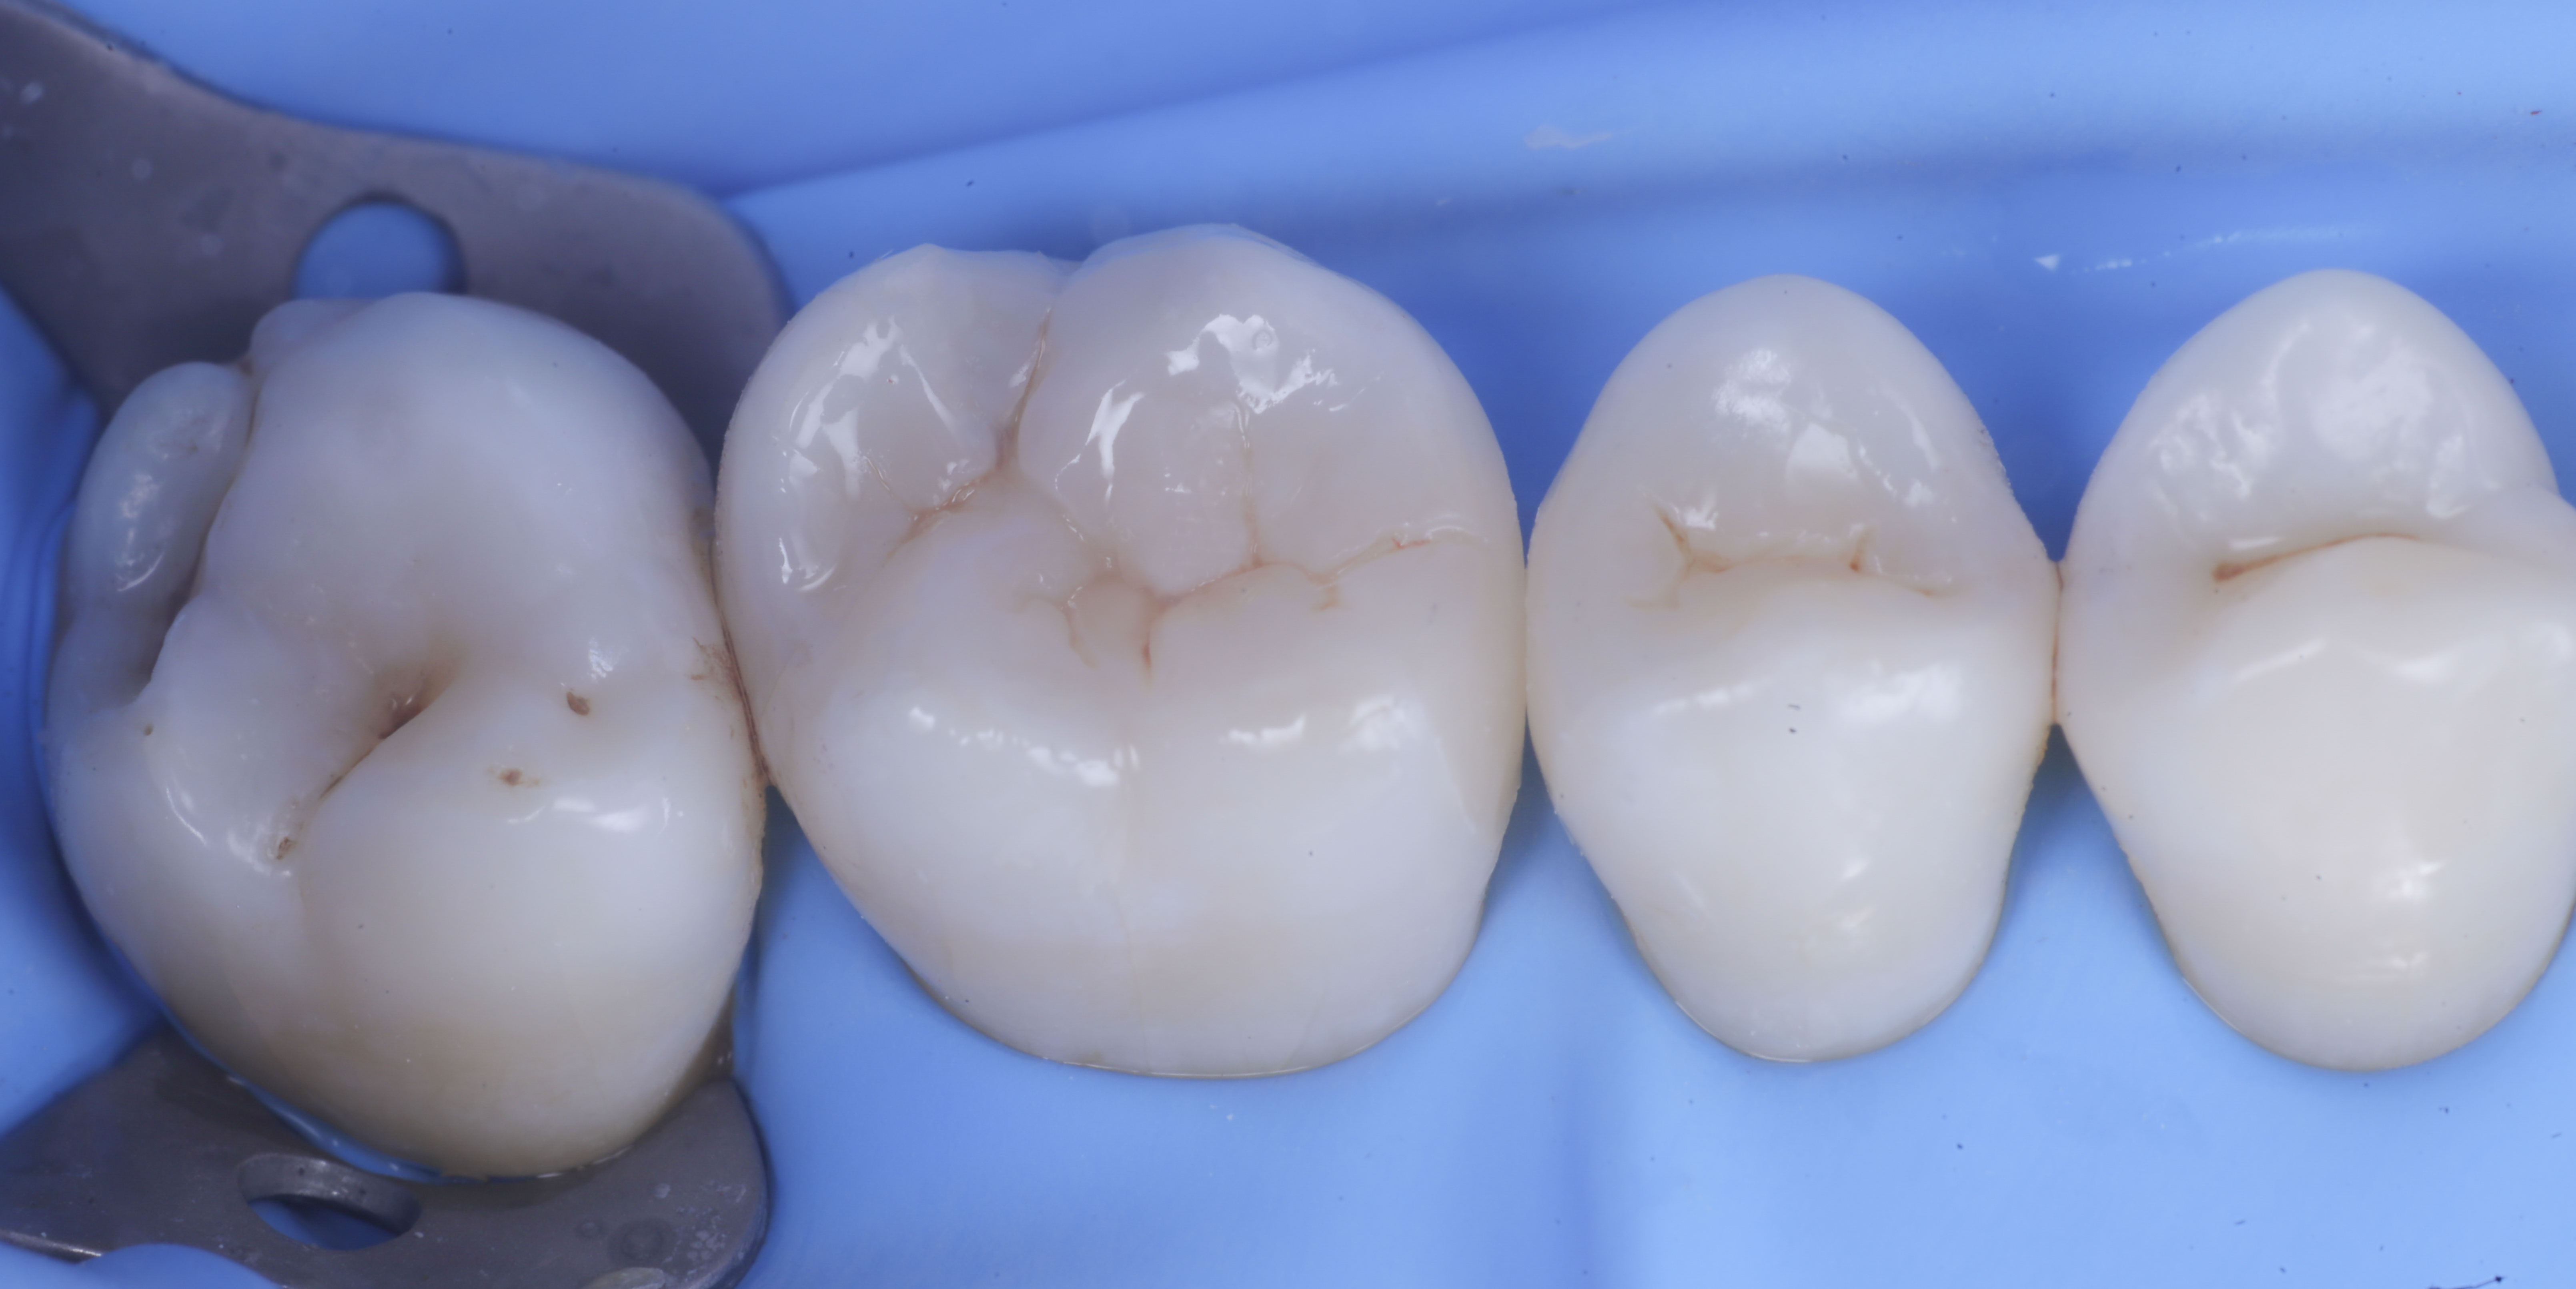

foto 1 Fotografia iniziale

Si presenta alla nostra attenzione per dolore in zona premolare e molare del primo quadrante. Dopo un’analisi clinica e strumentale con radiografie e test diagnostici, si evidenzia la necessità di sostituire le precedenti otturazioni in composito, al fine di consegnare un migliore punto di contatto (fenomeno dell’impact food).

Come spesso accade in queste circostanze si decide per il rifacimento di tali restauri sia su 1.6 che su 1.5.